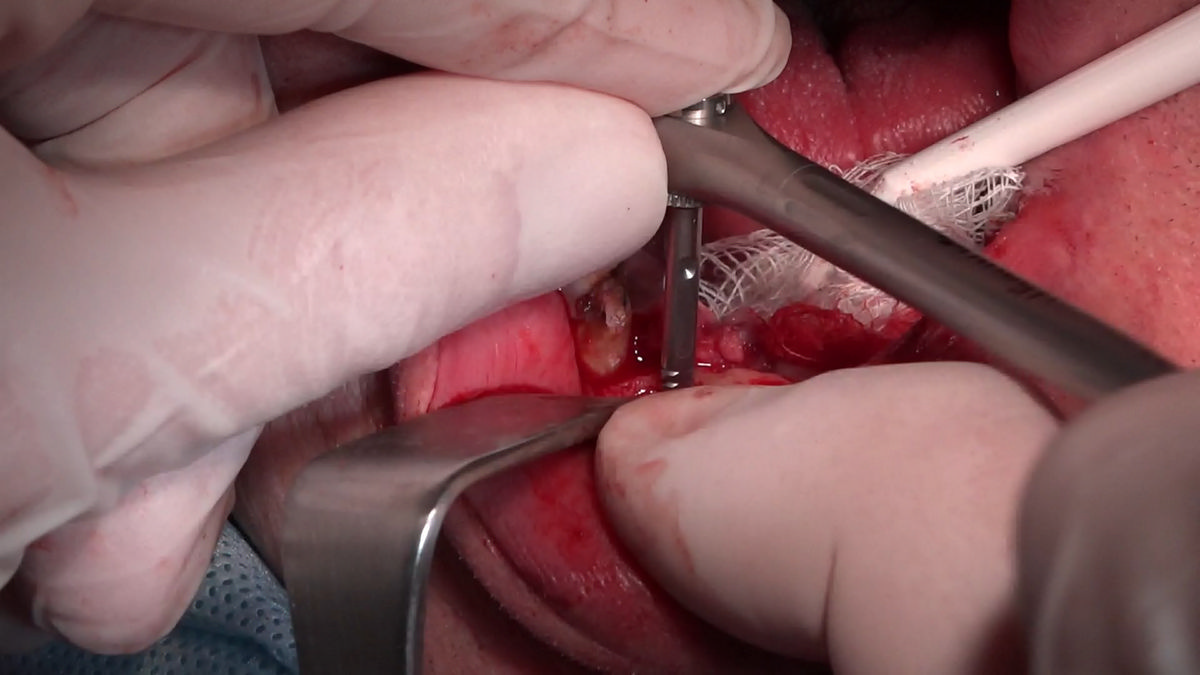

PRACTICULUM IMPLANTOLOGII - SEZON X - SESJA 4 - GRUPA B